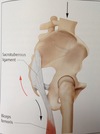

Femoroacetabular impingement image - Cam